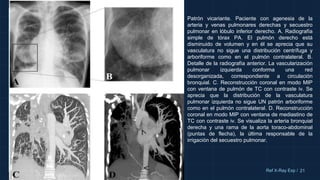

Patrón vicariante. Paciente con agenesia de la

arteria y venas pulmonares derechas y secuestro

pulmonar en lóbulo inferior derecho. A. Radiografía

simple de tórax PA. El pulmón derecho está

disminuido de volumen y en él se aprecia que su

vasculatura no sigue una distribución centrífuga y

arboriforme como en el pulmón contralateral. B.

Detalle de la radiografía anterior. La vascularización

pulmonar izquierda conforma una red

desorganizada, correspondiente a circulación

bronquial. C. Reconstrucción coronal en modo MIP

con ventana de pulmón de TC con contraste iv. Se

aprecia que la distribución de la vasculatura

pulmonar izquierda no sigue UN patrón arboriforme

como en el pulmón contralateral. D. Reconstrucción

coronal en modo MIP con ventana de mediastino de

TC con contraste iv. Se visualiza la arteria bronquial

derecha y una rama de la aorta toraco-abdominal

(puntas de flecha), la última responsable de la

irrigación del secuestro pulmonar.